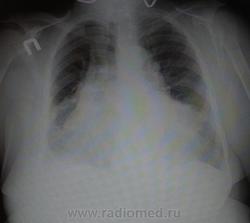

Ж., около 70 лет с терапии. Это все расширенная тень сердца? снимки со всех сторон https://radiomed.ru/sites/default/files/styles/case_slider_image/public/user/18943/w4cqokz5r48.jpg?itok=TtsqZxH3 https://radiomed.ru/sites/default/files/styles/case_slider_image/public/user/18943/b5pudnayjfk.jpg?itok=r5W2Bmm2 ID:47925 Втр, 10/12/2013 - 16:34 #1 Евгений Дорофеев Не на сайте Был на сайте: 11 лет 1 месяц назад Зарегистрирован: 06.06.2013 - 17:28 Публикации: 1746 Да, застой то приличный с гидротораксом, не считая того что укладка страдает. Втр, 10/12/2013 - 16:40 #2 НД Не на сайте Был на сайте: 9 лет 8 месяцев назад Зарегистрирован: 25.09.2013 - 21:06 Публикации: 319 все-таки с гидротораксом? укажите, пожалуйста )) Втр, 10/12/2013 - 16:59 #3 Евгений Дорофеев Не на сайте Был на сайте: 11 лет 1 месяц назад Зарегистрирован: 06.06.2013 - 17:28 Публикации: 1746 Если не секрет снимок лёжа выполнен? Втр, 10/12/2013 - 17:02 #4 Евгений Дорофеев Не на сайте Был на сайте: 11 лет 1 месяц назад Зарегистрирован: 06.06.2013 - 17:28 Публикации: 1746 НД wrote: все-таки с гидротораксом? укажите, пожалуйста )) А нижние границы на боковой поверхности ? Втр, 10/12/2013 - 17:02 #5 НД Не на сайте Был на сайте: 9 лет 8 месяцев назад Зарегистрирован: 25.09.2013 - 21:06 Публикации: 319 dorofey84 wrote: Если не секрет снимок лёжа выполнен? нет Втр, 10/12/2013 - 17:08 #6 НД Не на сайте Был на сайте: 9 лет 8 месяцев назад Зарегистрирован: 25.09.2013 - 21:06 Публикации: 319 dorofey84 wrote: НД wrote: все-таки с гидротораксом? укажите, пожалуйста )) А нижние границы на боковой поверхности ? а почему тогда купола визуализируются на прямом Втр, 10/12/2013 - 17:37 #7 Евгений Дорофеев Не на сайте Был на сайте: 11 лет 1 месяц назад Зарегистрирован: 06.06.2013 - 17:28 Публикации: 1746 Грубо конечно, но............. (про линии Керли)и кстати правый реберно диафрагмальный синус ...................Приложения: Втр, 10/12/2013 - 17:43 #8 НД Не на сайте Был на сайте: 9 лет 8 месяцев назад Зарегистрирован: 25.09.2013 - 21:06 Публикации: 319 dorofey84 wrote: Грубо конечно, но............. (про линии Керли)и кстати правый реберно диафрагмальный синус ................... но он все-таки проглядывает, в оригинале было видно, да и тут Втр, 10/12/2013 - 17:54 #9 Евгений Дорофеев Не на сайте Был на сайте: 11 лет 1 месяц назад Зарегистрирован: 06.06.2013 - 17:28 Публикации: 1746 НД wrote: dorofey84 wrote: Грубо конечно, но............. (про линии Керли)и кстати правый реберно диафрагмальный синус ................... но он все-таки проглядывает, в оригинале было видно, да и тут А вообще если я сомневаюсь то УЗИ плевральных полостей заказываю, но это я............ Втр, 10/12/2013 - 18:03 #10 НД Не на сайте Был на сайте: 9 лет 8 месяцев назад Зарегистрирован: 25.09.2013 - 21:06 Публикации: 319 это вы хорошо про узи напомнили Втр, 10/12/2013 - 18:12 #11 Mila85 Не на сайте Был на сайте: 3 года 1 месяц назад Зарегистрирован: 15.03.2012 - 16:59 Публикации: 1790 Может и есть небольшое количество жидкости, но какое это имеет по большому счету значение? Тень сердца резко расширена, огромная ВПВ Втр, 10/12/2013 - 18:56 #12 Евгений Дорофеев Не на сайте Был на сайте: 11 лет 1 месяц назад Зарегистрирован: 06.06.2013 - 17:28 Публикации: 1746 Mila85 wrote: Может и есть небольшое количество жидкости, но какое это имеет по большому счету значение? Тень сердца резко расширена, огромная ВПВ +1 Только на пункции до 500 мл жидкости светло жёлтой слабо опалесцирующей получали. Втр, 10/12/2013 - 22:40 #13 И.Бондаренко Не на сайте Был на сайте: 2 дня 11 часов назад Зарегистрирован: 13.09.2011 - 22:55 Публикации: 9206 Жидкость есть. Количество можно узнать по латерограмме или УЗИ. Втр, 10/12/2013 - 23:02 #14 НД Не на сайте Был на сайте: 9 лет 8 месяцев назад Зарегистрирован: 25.09.2013 - 21:06 Публикации: 319 Спасибо всем! Пт, 13/12/2013 - 01:25 #15 Makcimalist Не на сайте Был на сайте: 11 лет 9 месяцев назад Зарегистрирован: 08.05.2010 - 14:28 Публикации: 1994 Интересно, не только количество выпота справа (по УЗИ), но и сколько её в перикарде. Если возможно, дообследование будет - данные сообщите. Заранее Вам спасибо. -------------- "Просто, по видимости, не видеть логики в очевидных вещах - это тоже одно из свойств некоторых умов, наряду с грустными думами о свойствах ума других." © Vega 08/10/2011

Да, застой то приличный с гидротораксом, не считая того что укладка страдает.

Может и есть небольшое количество жидкости, но какое это имеет по большому счету значение? Тень сердца резко расширена, огромная ВПВ

Жидкость есть. Количество можно узнать по латерограмме или УЗИ.

Интересно, не только количество выпота справа (по УЗИ), но и сколько её в перикарде. Если возможно, дообследование будет - данные сообщите. Заранее Вам спасибо.